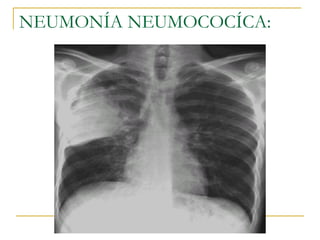

NEUMONIA NEUMOCÓCICA Más frecuente de N. Extrahospitalaria La infección genera inmunidad parcial Infección vírica Daña pulmones Neumococo INFECCIÓN

NEUMONÍA NEUMOCOCÍCA: